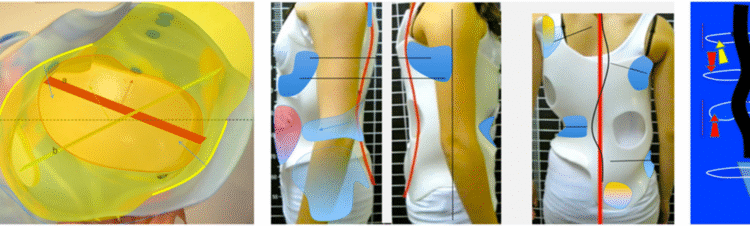

الإجابة الحديثة التي توصلت إليها الأبحاث تشير إلى أن شكل العمود الفقري والقفص الصدري ثلاثي الأبعاد (3D) قبل وأثناء ارتداء الحزام يُعد عاملًا حاسمًا في تحديد فعالية العلاج.

لذلك، أصبح من الضروري دراسة العمود الفقري والقفص الصدري في الثلاثة مستويات معًا لفهم مدى استجابة الطفل للحزام.

6. الشكل المحوري للعمود الفقري

عند النظر للعمود الفقري من الأعلى، يمكن أن يكون:

على شكل S

أو على شكل V

هذا الاختلاف يؤثر على كيفية توزيع الضغط داخل الحزام، وبالتالي على فعالية العلاج.

ومن هنا تأتي أهمية تصميم الحزام بشكل فردي لكل طفل.

لذلك، الأحزمة المصممة خصيصًا بناءً على التحليل ثلاثي الأبعاد تحقق نتائج أفضل من الأحزمة التقليدية العامة.

التطور الكبير في تصميم الأحزمة الطبية جعل علاج اعوجاج العمود الفقري عند المراهقين أكثر نجاحًا وأقل إزعاجًا. باستخدام تقنيات التصوير الثلاثي الأبعاد والمحاكاة الرقمية، أصبح الحزام أكثر خفة وراحة، ويعطي نتائج أفضل في تصحيح الانحناء والتواء العمود الفقري.